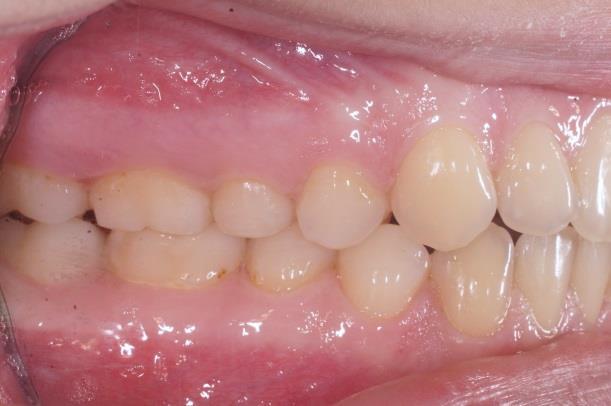

Les élastiques reliant les dents du haut et les dents du bas seront prescrits par l’orthodontiste, suivant la déformation des mâchoires et la sévérité. Changez vos élastiques au moins une fois par jour, ils ont tendance à se détériorer et perdre leur force après 24 heures.

Les propulseurs permettent de corriger les déformations sévères avec un maximum d’efficacité ce sont des accélérateurs de croissance , ils sont fixes sur les bagues pendant 3 mois puis sont enlevés pour être remplacés par des élastiques.